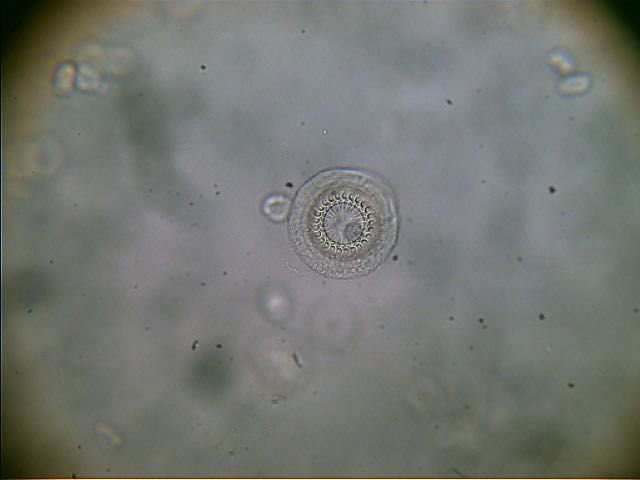

Diagnostik

am lebenden, betäubten Fisch (Mikroskopie, Parasitologie)